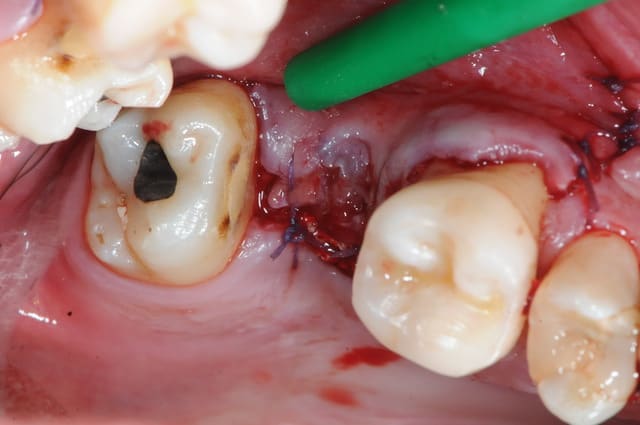

4: incision décalée en palatin par rapport au trou de la cbs (pas trop car après il y a risque de nécrose)

5: en général, il ya décollement assez facile entre la membrane de schneider et le palais.

1&2 : réalisation à l'aide d'une tréphine de la fenêtre vestibulaire pour aller plus vite et surtout pour pouvoir réutiliser plus tard ce petit bloc osseux.

( vous verrez plus atrd à quoi ça sert)

3: fenêtre et CBS bien visibles

j'aurai aimé faire mon abord latéral plus haut, mais je vous rappel que l'on est au niveau de la 7 et que c'est difficile d'écarter les tissus.

(Rachel qui m'a gentiment assisté à beaucoup souffert de tétanisation musculo-palmaire multiple)

vous noterez tout de suite la différence de teinte entre un sinus sain et avec ici, un sinus hyper inflammatoire et infecté (une vraie cocotte-minute)